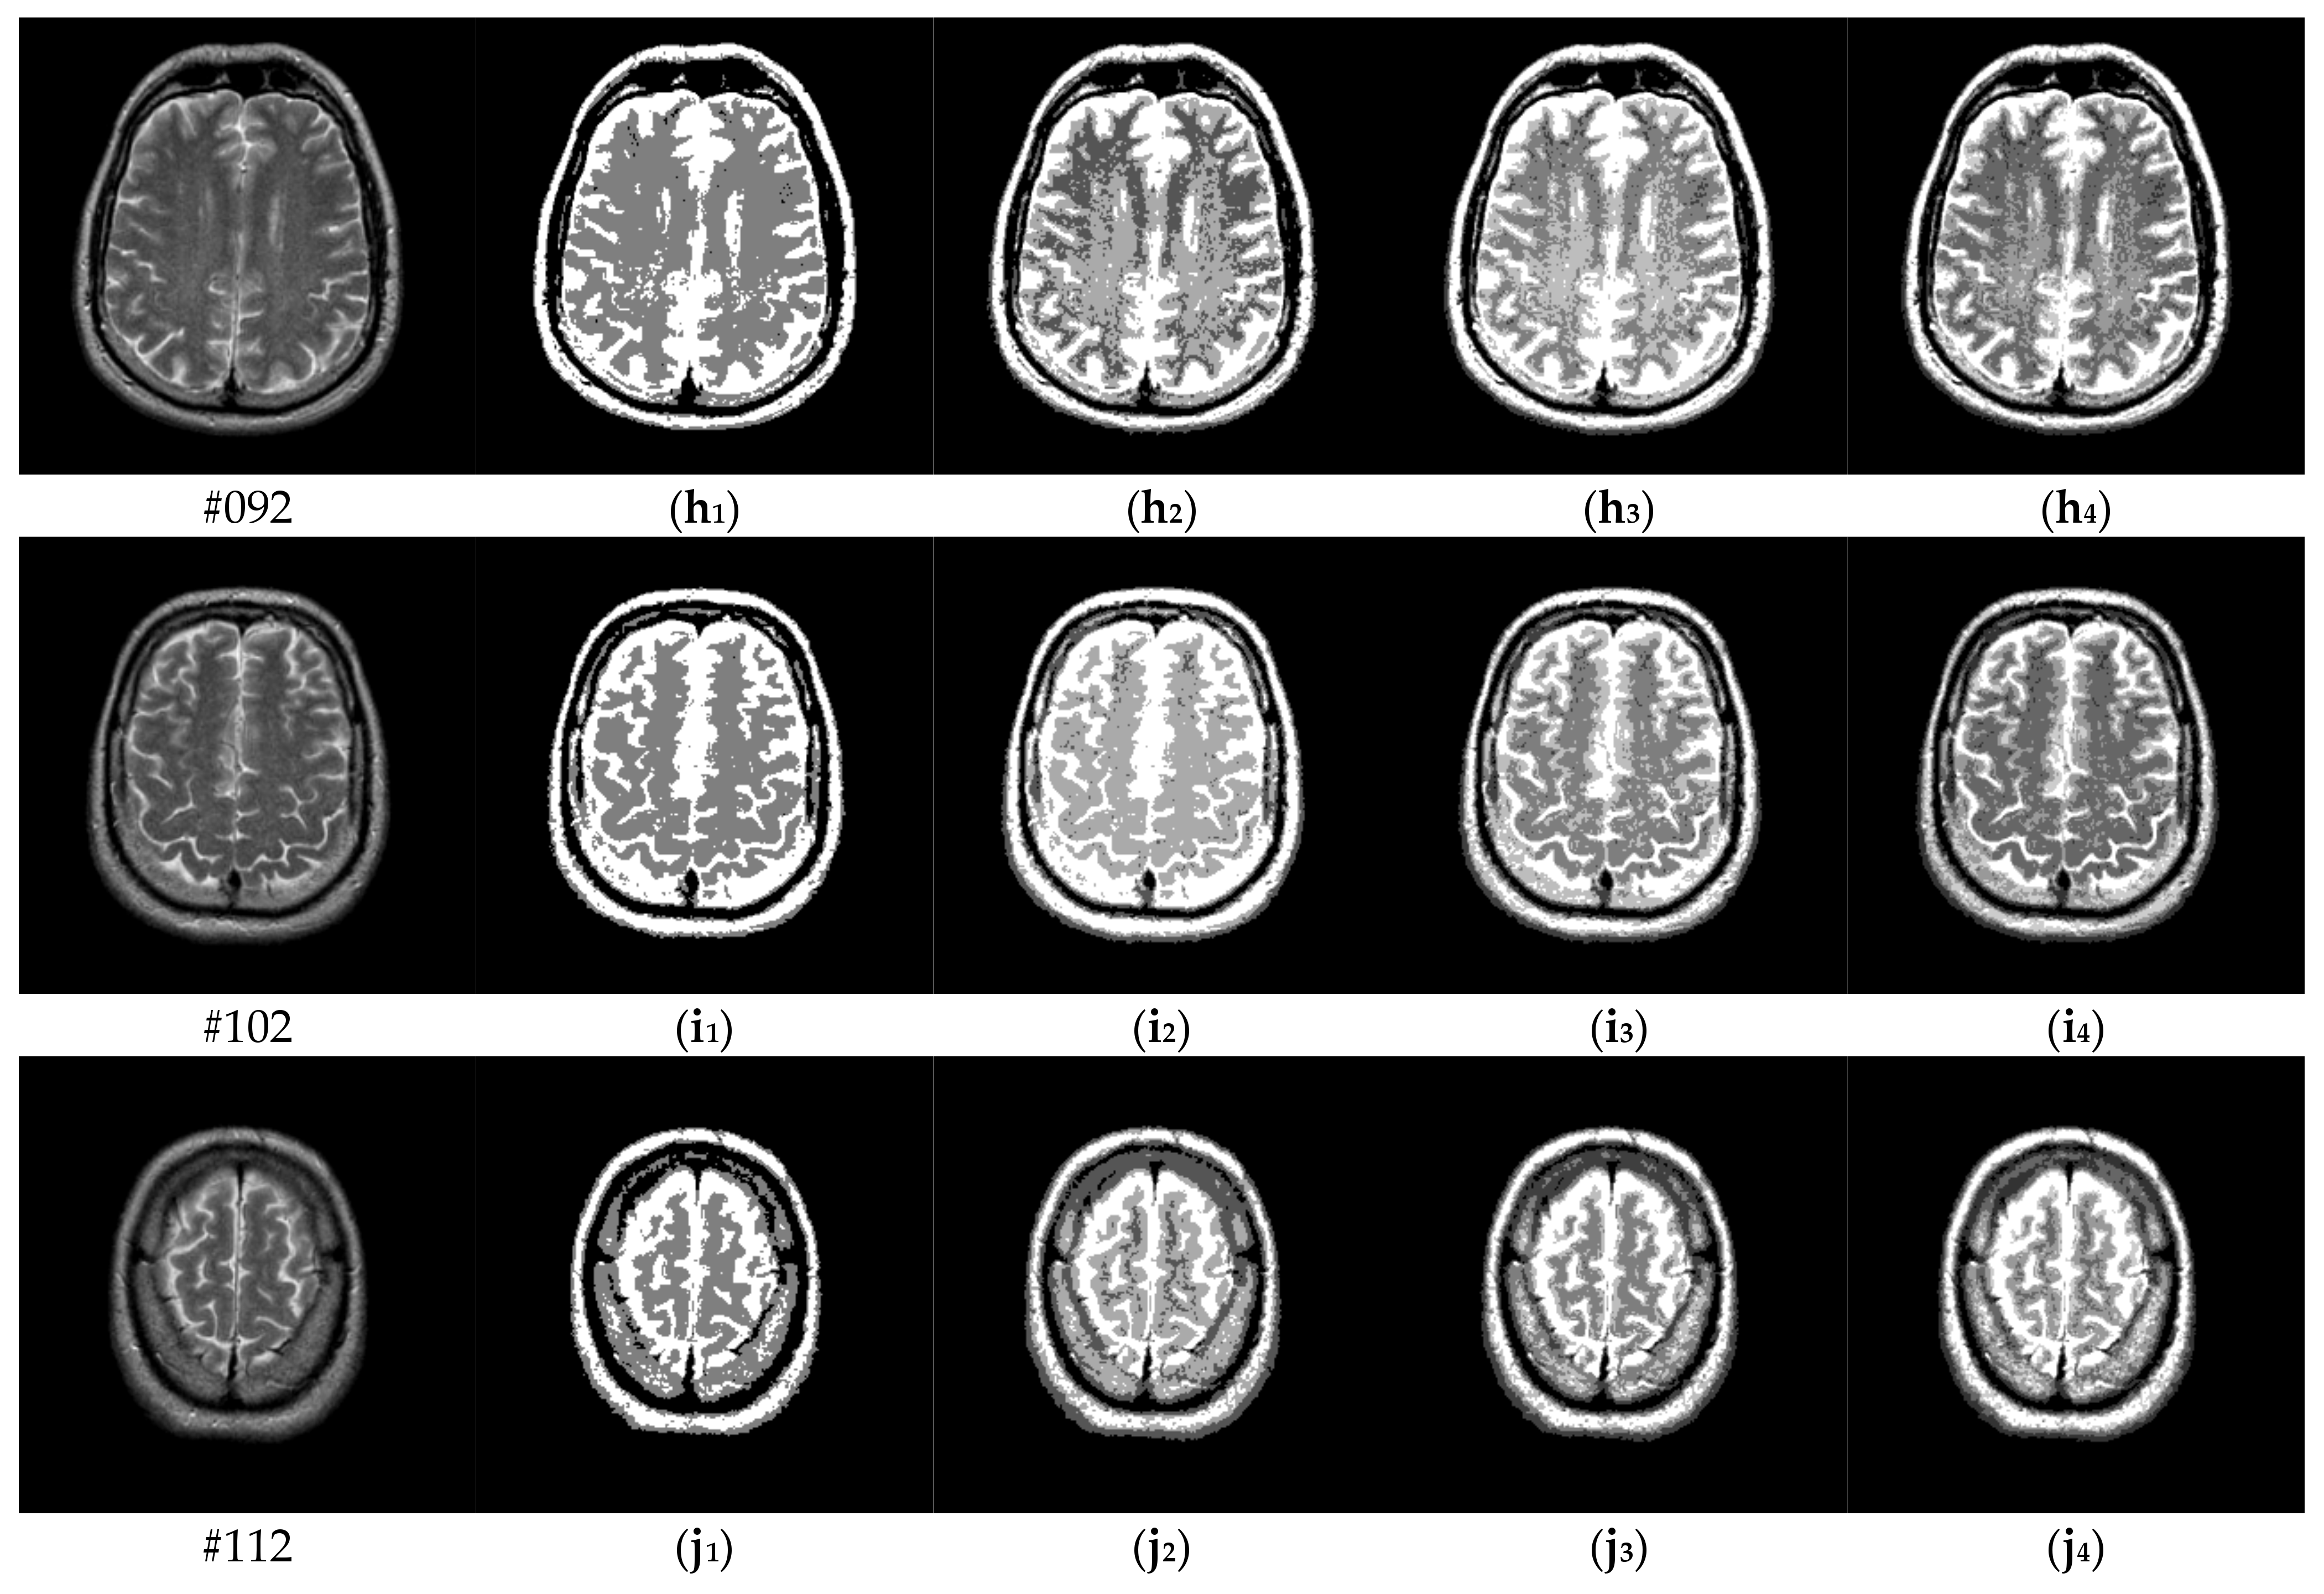

To verify the performance of the proposed algorithm, five representative multi-threshold segmentation algorithms are selected for comparative experiments. The five comparative experimental algorithms are: (1) image threshold segmentation algorithm based on particle swarm optimization (PSO), (2) image threshold segmentation algorithm based on bacterial foraging (BF), (3) image threshold segmentation algorithm based on adaptive bacterial foraging (ABF), (4) image threshold segmentation algorithm based on Nelder-Mead simplex (NMS), (5) image multi-threshold segmentation algorithm based on real coded genetic algorithm (RCGA) [43]. The number of thresholds is set to K = 2, 3, 4, and 5, respectively. Due to the limited space, we only show the segmentation results of the proposed algorithm in this paper. Figure 8 shows the segmentation results of Slice#022~#112 when the threshold K = 2, 3, 4, 5. Intuitively, the proposed algorithm can better segment each region of the experimental image, and the continuity of different regions is well guaranteed. At the same time, the visual effects are satisfactory.

Figure 8.

Segmentation results obtained by the proposed algorithm for brain slices #022~#112; (a1–j1) display the results of 2-thresholding; (a2–j2) display the results of 3-thresholding; and (a3–j3) display the results of 4-thresholding; (a4–j4) display the results of 5-thresholding.